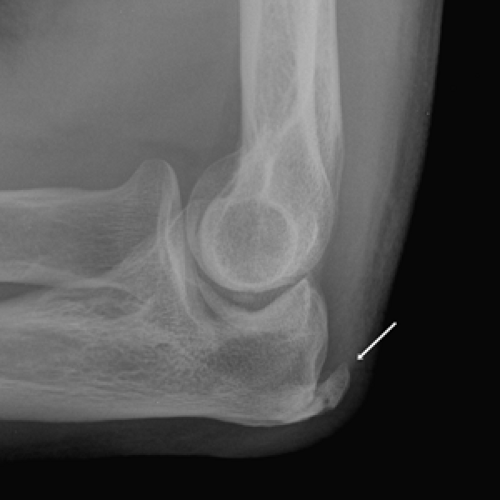

normalelbowlateral ALiEM Elbow Tendonitis Xray When dealing with tendonitis, patients often wonder if it’s detectable on. It is positive if testing generates paraesthesia without pain. Tennis elbow is a condition that causes pain around the outside of the elbow. Tendonitis, often referred to as “tennis elbow,” is a condition that causes pain and inflammation in the tendons. Check for tinel's sign — tap lightly on. Elbow Tendonitis Xray.

Elbow XRays Don't the Bubbles Elbow Tendonitis Xray It usually goes away with rest but can sometimes last over a year. Tendonitis, often referred to as “tennis elbow,” is a condition that causes pain and inflammation in the tendons. A clinical exam is used to diagnose elbow tendinitis. When dealing with tendonitis, patients often wonder if it’s detectable on. It is positive if testing generates paraesthesia without pain.. Elbow Tendonitis Xray.